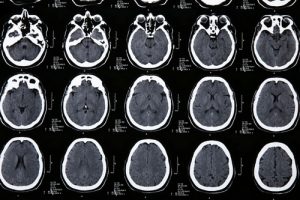

Израильские врачи всегда одними из первых внедряют в практику инновационные медицинские технологии. Касается это и такого направления, как нейрохирургия – операции на головном мозге в клиниках Израиля выполняются с применением самых передовых методик, позволяющих минимизировать повреждения черепа или вовсе исключать их. Благодаря такому подходу операционные риски для пациентов сводятся практически к нулю, а период восстановления становится менее болезненным и более быстрым.

Отзывы об операциях на головном мозге в Израиле свидетельствуют о том, что для местных специалистов нет неразрешимых задач. Даже если патологический очаг локализируется в труднодоступном участке, нейрохирурги клиник Земли обетованной способны подобрать действенные методы его устранения. По этой причине большинство жителей стран СНГ, узнав о необходимости выполнения хирургического вмешательства на мозге, отправляются на лечение именно в Израиль. Здесь им обеспечена максимально квалифицированная медицинская помощь, которая гарантированно дает положительные результаты.

Среди главных условий успешности операций на мозге не только высокий уровень профессионализма врачей и применение современных хирургических технологий, но и своевременность диагностики патологии. Как показывает опыт израильских нейрохирургов, на ранних стадиях прогрессирования болезни шансов на полное излечение намного больше, чем при ее запущенных формах. В клиниках Израиля пройти высокоточное обследование может каждый – это занимает не более трех-четырех дней, а цены на диагностические процедуры являются вполне доступными. В случае обнаружения в головном мозге патологического очага, требующего хирургического иссечения, могут быть использованы следующие методы терапии: